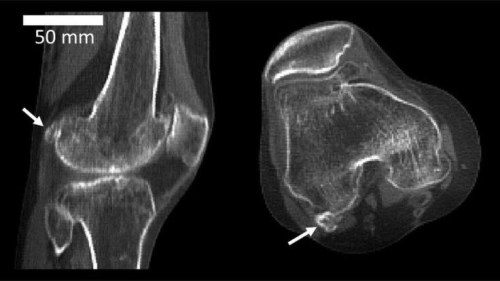

Sore knee? Maybe You Have a Fabella

The BBC has an interesting little piece about a small extra (sesamoid) bone that seems to be more common now than even just a hundred years ago, even though other sesamoid bones elsewhere in the body are not becoming more common.

The fabella (“little bean” in Latin) can be the cause of knee pain and perineal nerve palsy.

“Between 1918 and 2018, reports of the fabella bone’s existence in the knee increased to the extent that it is now thought to be three times as common as 100 years ago.

The scientists’ analysis showed that in 1918, fabellae were present in 11% of the world population, and by 2018, they were present in 39%.”

“Hou (2016) recently investigated the effects of the fabella on posterolateral pain and palsy of common peroneal nerve following total knee arthroplasty. During trials, fabellae were excised from some patients but left in others. Post‐surgery, posterolateral pain and palsy of common peroneal nerve were only observed in patients who still had fabellae. Accordingly, Hou recommended removing the fabella when knee replacement surgery is performed.”